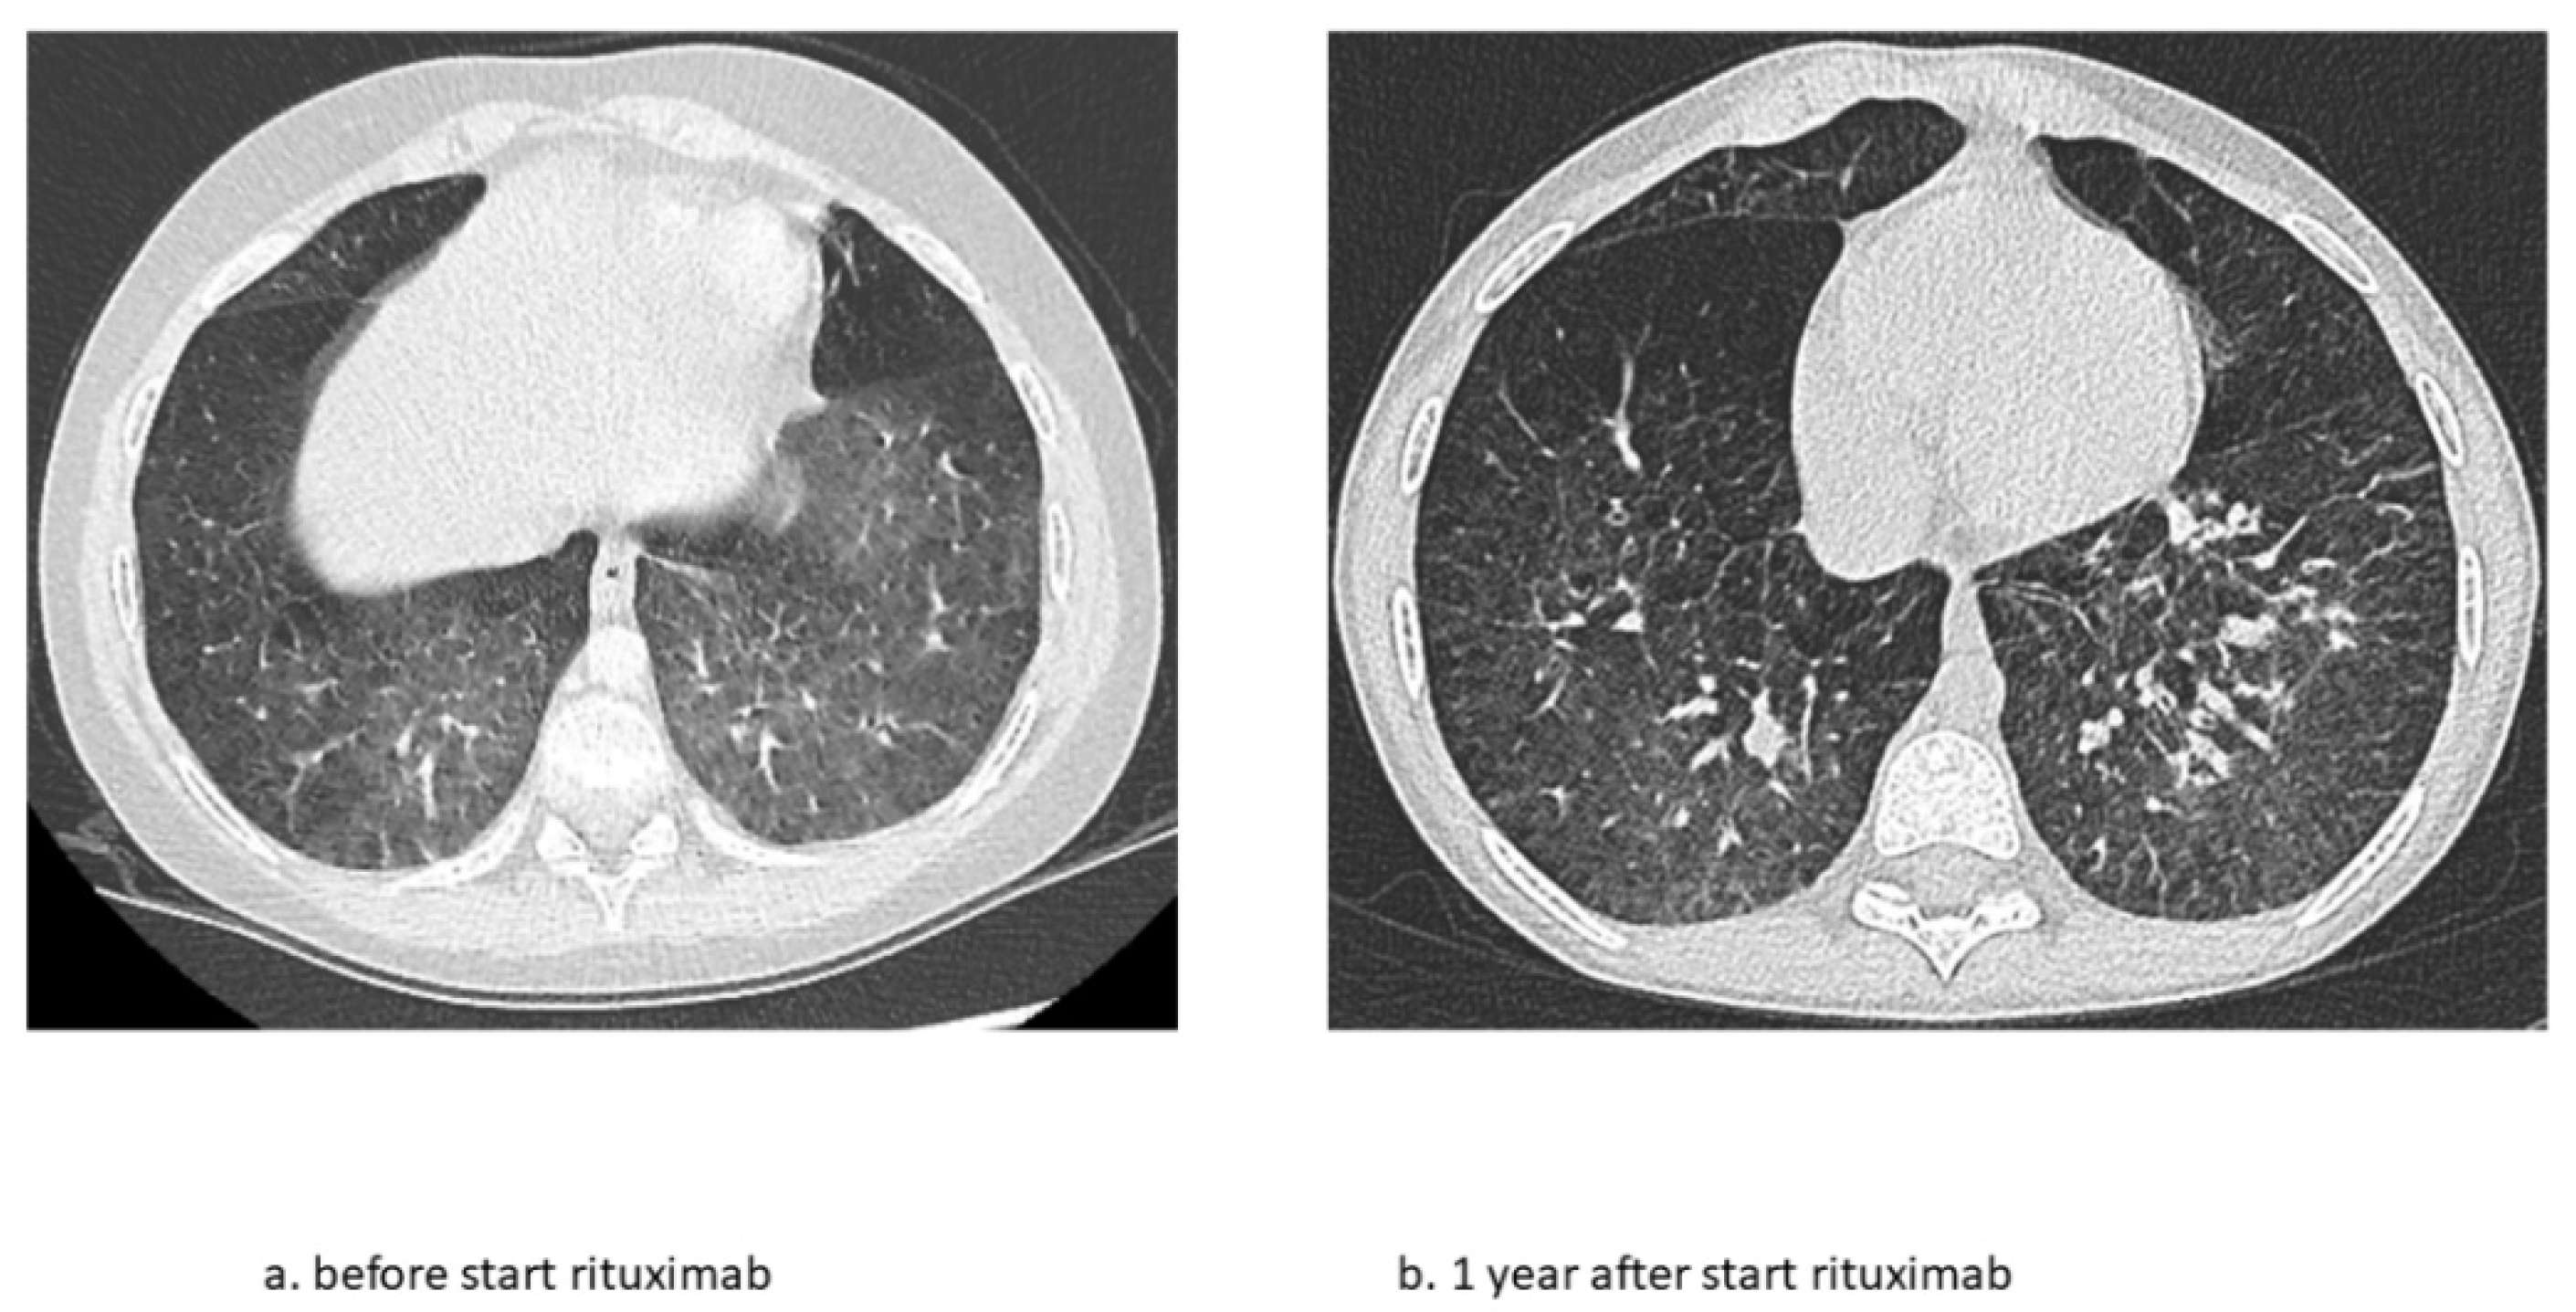

At the age of 9 years, RTX treatment was started. In the following 5 years, he experienced only two exacerbations for which he needed treatment with methylprednisolone. Maintenance treatment with oral prednisolone was tapered and stopped at the age of 10. Adrenal insufficiency still remains but maintenance treatment with hydrocortisone has now been gradually lowered. Chest CT scans showed fewer ground glass opacifications but an increase in interlobular septal thickening over time in accordance with the previous years of severe exacerbations and instable disease (Figure 1). The patient’s lung function, which had been rapidly declining, now shows a gradual increase in forced vital capacity (Figure 2). In addition, the fatigue that severally hampered his daily activities has improved considerably. Due to the RTX treatment, his IgG levels declined just below the normal limit (4.9 g/L). After recurrent viral respiratory infections resulting in two milder IPH exacerbations (the first shortly after the start of RTX treatment, while for the second no admission was needed), suppletion with intravenous immunoglobulins (IVIG) was started. Since then, no outbreaks of IPH have occurred. His height is catching up after steroid administration was stopped following stunted growth for many years (Figure 3). Due to new diagnostic possibilities, he was screened in 2019 for interferonopathy, which showed a mild elevated interferon type 1 signature. Nevertheless, genetic testing showed no abnormalities, specifically, no signs of the then newly described COPA syndrome (coatomer protein complex subunit alpha), for which JAK-inhibition might have been an effective treatment. In conclusion, RTX treatment is well-tolerated with mild hypogammaglobulinemia, for which he receives supplemental immunoglobulin therapy every 6 weeks.

Figure 1. Chest CT scan images before and 1 year after start of RTX treatment during clinically stable disease phase. (a) Shows ground glass opacifications as main abnormality and (b) less well-defined ground glass but more interlobular septal thickening after 1 year of RTX.